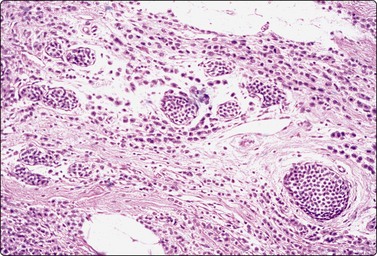

image

Fig. 7.27 Fibroadenoma

Tissue sections from same case as Figure 7.24; (A) Low power: typical appearances of fibroadenoma; (B) High power: ductal structures lined by atypical epithelium with enlarged vesicular nuclei and a few mitoses (H&E).